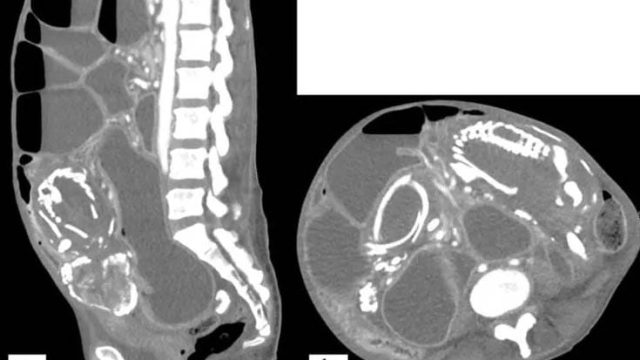

Ao chegar nos Estados Unidos, exames de imagem confirmaram que se tratava de um caso de litopédio, que é quando o feto se desenvolve no abdômen e não no útero, gerando a calcificação. Essa complicação da gravidez é extremamente rara e pode permanecer assintomática.

Após o diagnóstico, foi indicado que ela passasse por uma cirurgia para retirar o feto e assim desobstruir o intestino. No entanto, por medo do procedimento, ela recusou e acabou morrendo por desnutrição 14 meses após chegar ao país. Isso ocorreu porque a presença do feto impedia a absorção eficiente de nutrientes e comprimia os demais órgãos.